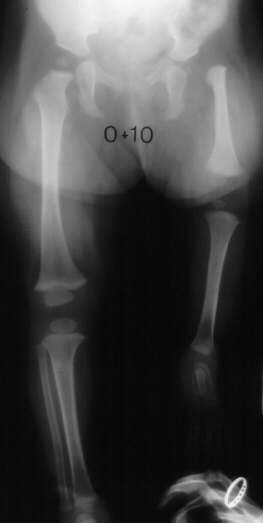

The

correct diagnosis for this pattern of deformity is proximal femoral

focal deficiency (PFFD).

This

is a common combination of deformities.

With

today's technique the best treatment for congenital limb length

discrepancy is lengthening after age five.